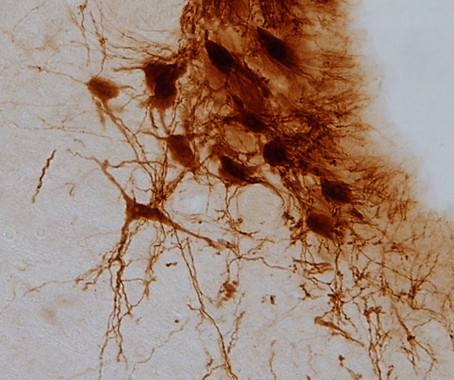

Neuronas de locus cerúleo. (Foto: Fundación Descubre)

El locus cerúleo es el principal productor de noradrenalina del cerebro, una biomolécula involucrada en la transmisión del mensaje nervioso entre las neuronas y que desempeña un papel importante en la ansiedad y la depresión.